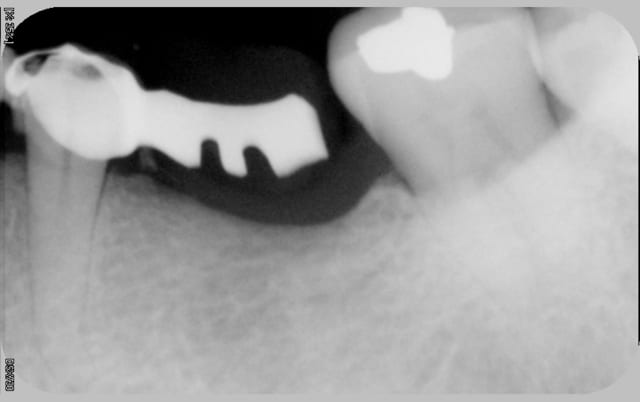

je vois cette patient de 62 ans pour la premiére fois en novembre 2010, elle me demande une rehabilitation des secteurs édentés, sont absentes 14, 15, 47,et 36 toutes les autres dents sont ultra saines, pas de tartre, un excellent controle de plaque, seul "hic" la patient à une valvulopathie qui la classe dans les patients à risque A...

Puis le temps passe, elle reviens en urgence la semaine derniére pour une pulpite et saignement des gencicves,

et là je découvre ça...(cf radio) fait au bled il y a un mois, pour une fortune là bas en depis de tout ce qu'on s'est acharné à lui expliquer. dommage.

de toute façon là il n'y à plus rien à faire, valvulopathie à risque d'endocardite il n'y a pas de trt radiculaire qui tienne c'est l'avulsion directe (sauf eventuellement pour la 35)en cas de pathologie pulpaire. ce qui m'embete c'est le bridge 14-16 qui génère une gingivite chronique ce qui n'est pas moins dangereux au regard du risque d'endocardite.